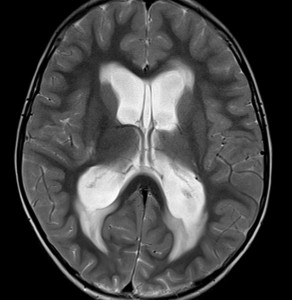

T2強調画像です。拡大した脳室の周囲に白くにじむような髄液のしみ出しがあります。脳室の周囲浮腫が出てくると頭痛や嘔吐が強くなります。